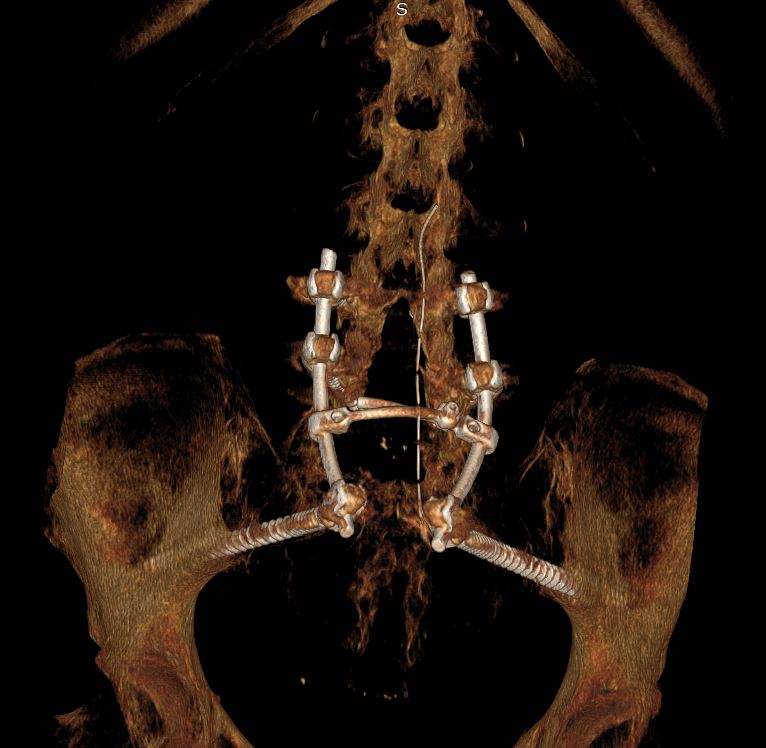

Αποφασίστηκε η διενέργεια αρχικά σπονδυλόδεσίας της κατώτερης οσφυικής μοίρας με το ιερό οστό και τα λαγόνια. Στη συνέχεια ακολούθησε ολική εξαίρεση του όγκου (σβάννωμα)

Ξεκινήσαμε το χειρουργείο με σπονδυλοδεσία Ο4-Ο5-Ιερολαγόνια. Αφού εξασφαλίσαμε τη στήριξη της σπονδυλικής στήλης, προχωρήσαμε σε ολική εξαίρεση της βλάβης. Η συνολική διάρκεια του χειρουργείου ήταν 11 ώρες.